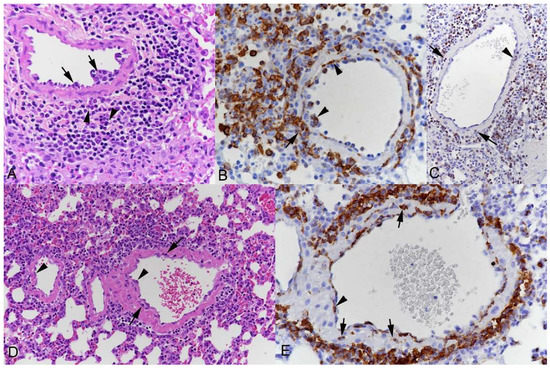

3.1. Pulmonary Vasculitis Is a Consistent Feature of SARS-CoV-2 Infection in Mouse Models

3.2. Respiratory Virus Infections, with Variable Degree of Alveolar Damage, and with or without Damage to Respiratory Epithelium, Elicit a Stereotypic Vascular Response

3.4. The Vascular Response after Respiratory Virus Infections Is Associated with Increased Expression of Adhesion Molecules in the Lungs